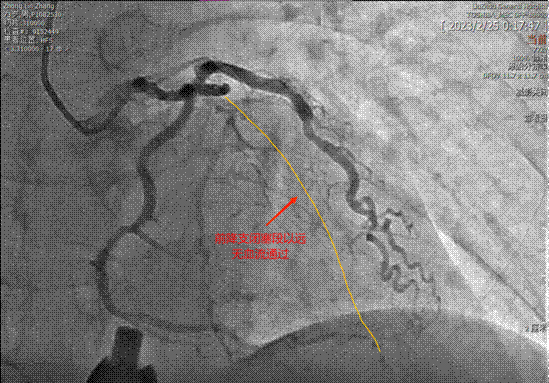

▲左主干-前降支-回旋支嚴重鈣化狹窄

▲閉塞的前降支

日前,鐘老伯因突發急性非ST段抬高型心肌梗死被送入柳州市人民醫院,急診介入團隊快速響應,進行了相應檢查。看到患者冠脈造影結果不禁讓人心驚膽寒,鐘老伯的冠脈三支血管嚴重鈣化,雪上加霜的是其中右冠脈、前降支慢性完全閉塞,左主干嚴重狹窄,僅存的回旋支開口至近段狹窄90%,再加上其合并有高血壓、高脂血癥、雙下肢深靜脈血栓形成、心力衰竭、近期有大型手術病史……真可謂是命懸一線!

術中,心血管內科二病區副主任王勇在ECMO輔助下順利將導絲通過前降支閉塞病變處。正如術前評估,IVUS檢查提示該患者左主干、前降支、回旋支多處360°環狀鈣化并管腔嚴重狹窄,且患者血管存在不同程度迂曲及成角,如應用冠脈內旋磨等方法處理,冠脈穿孔、破裂風險陡增,因此使用IVL處理鈣化病灶是最優選擇。術者先后應用Shockwave 3.5×12mm沖擊波球囊分別于左主干-前降支、回旋支環狀鈣化病變處共計觸發8個周期的沖擊波鈣化斑塊碎裂術,經IVUS證實鈣化環多點碎裂松解效果滿意,血管充分預擴張后順利完成分叉病變的支架植入,手術取得圓滿成功。